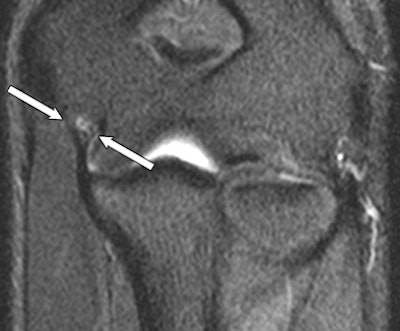

| Coronal STIR MR image of a 24-year-old man shows increased signal intensity in the proximal portion of the anterior UCL (arrows). |